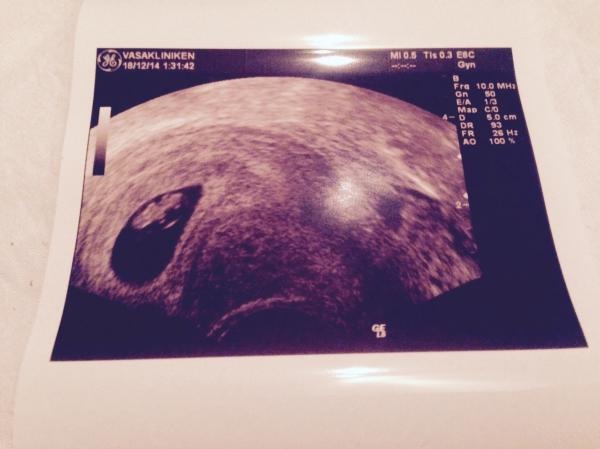

Här är "Peanut", som vi kallar bebisen för ca 2 veckor sen, hela 7.2 mm lång! :)